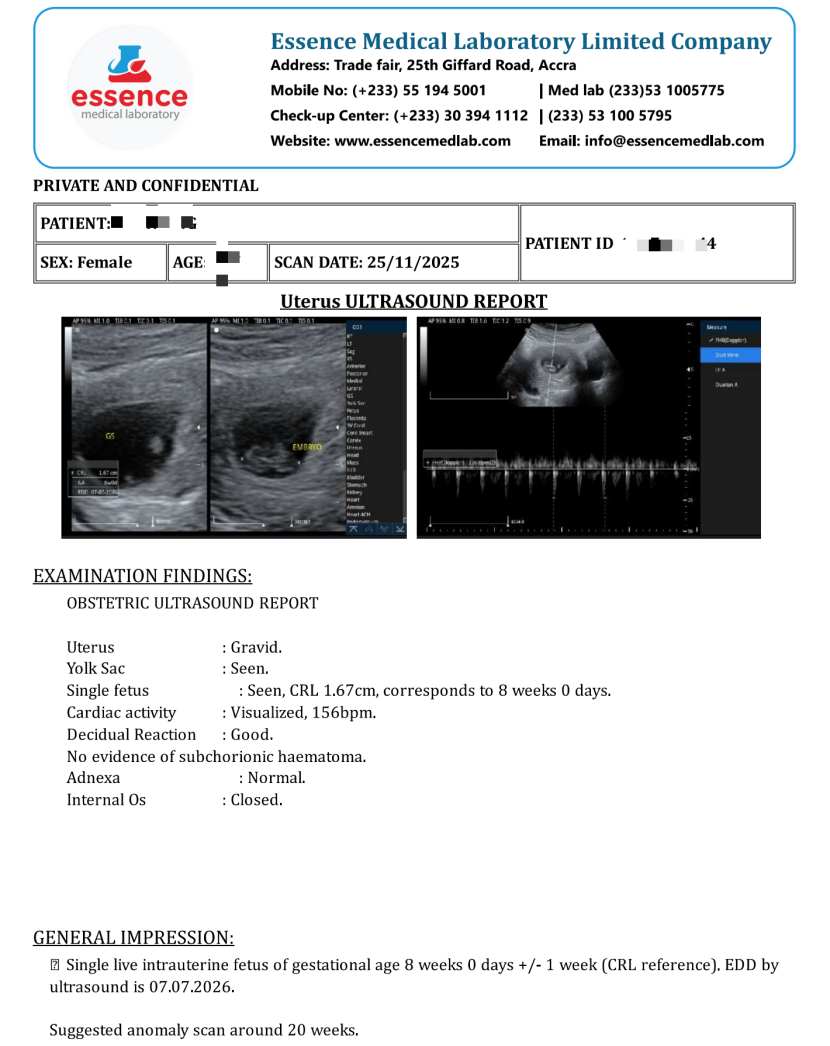

金盘公司凭借在医疗信息化和医学图像处理的优势,为基层诊所、医疗机构量身打造影像检查智慧云平台。HCOWA与金盘联合落地的远程影像AI 辅助诊断系统精准契合医患需求,当日,系统首次完整地出具了加纳第一批放射、超声检查AI图文报告。

传统模式下,医生书写报告后缺乏有效审核,易出现疏漏错误。金盘公司的 AI 辅助诊断系统如同严谨的医学专家,具备强大的报告审核功能。它能精准识别报告中的语法错误和用词不当,还能依据医学知识库和临床案例数据评估诊断结论和病情描述的准确性,对提升影像报告质量作用显著。

该系统引入先进 的AI 技术,发现问题后,系统会立即反馈并提供修正建议,帮助医生完善报告。严谨高效的图文报告得到了医生、患者的高度认可。